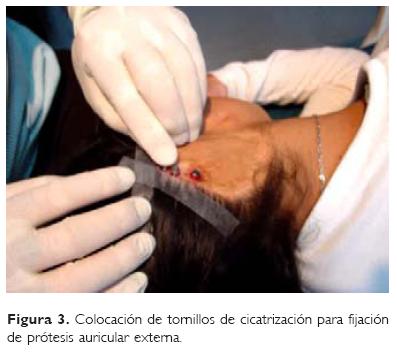

Procedimiento quirúrgico. El procedimiento se divide en dos estadios: I. Se realiza resección de remanentes, se levanta un colgajo dermograso y perióstico, se colocan tres implantes osteointegrados de titanio comercialmente puro en el área correspondiente a la concha, sobre el proceso mastoideo (Fig. 2). Sutura por planos. II. Posterior a seis meses de integración, se procede a la colocación de tornillos de cicatrización para fijación de las prótesis auriculares externas de silicon (Fig. 3).